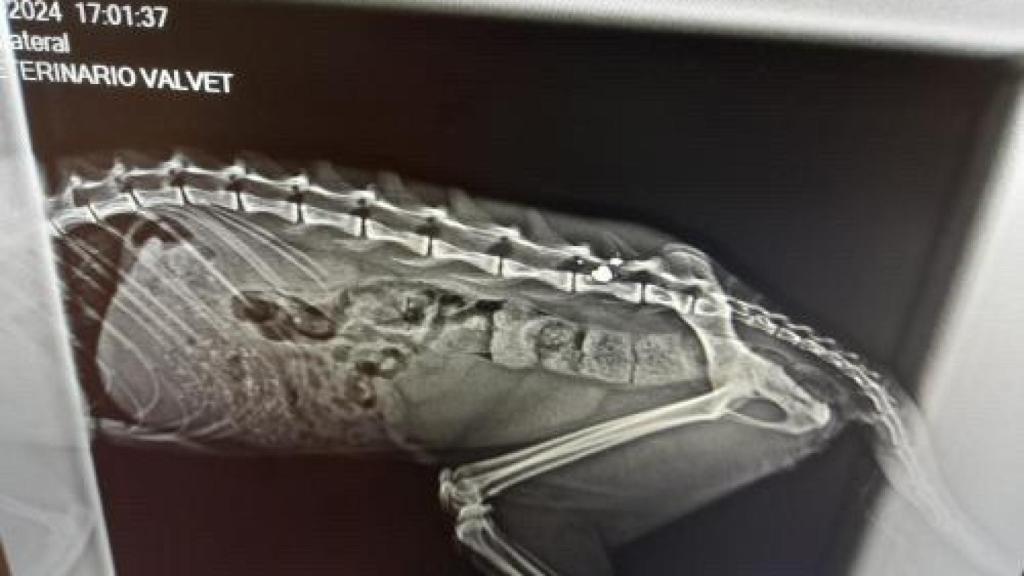

Imagen de una radiografía de un gato herido con un perdigón

Imagen de una radiografía de un gato herido con un perdigón Imagen cedida

La inquina de algunos vecinos contra estos animales no solo se está viendo como objeto los gatos de las colonias controladas sino también de los propios particulares ya que se ha conocido que hasta dos gatos de vecinos fueron víctimas de perdigones: "Uno nos lo encontramos muerto y otro con las patas llenas de sangre y un perdigón en la columna que fue incompatible con la vida", señala Asensio.